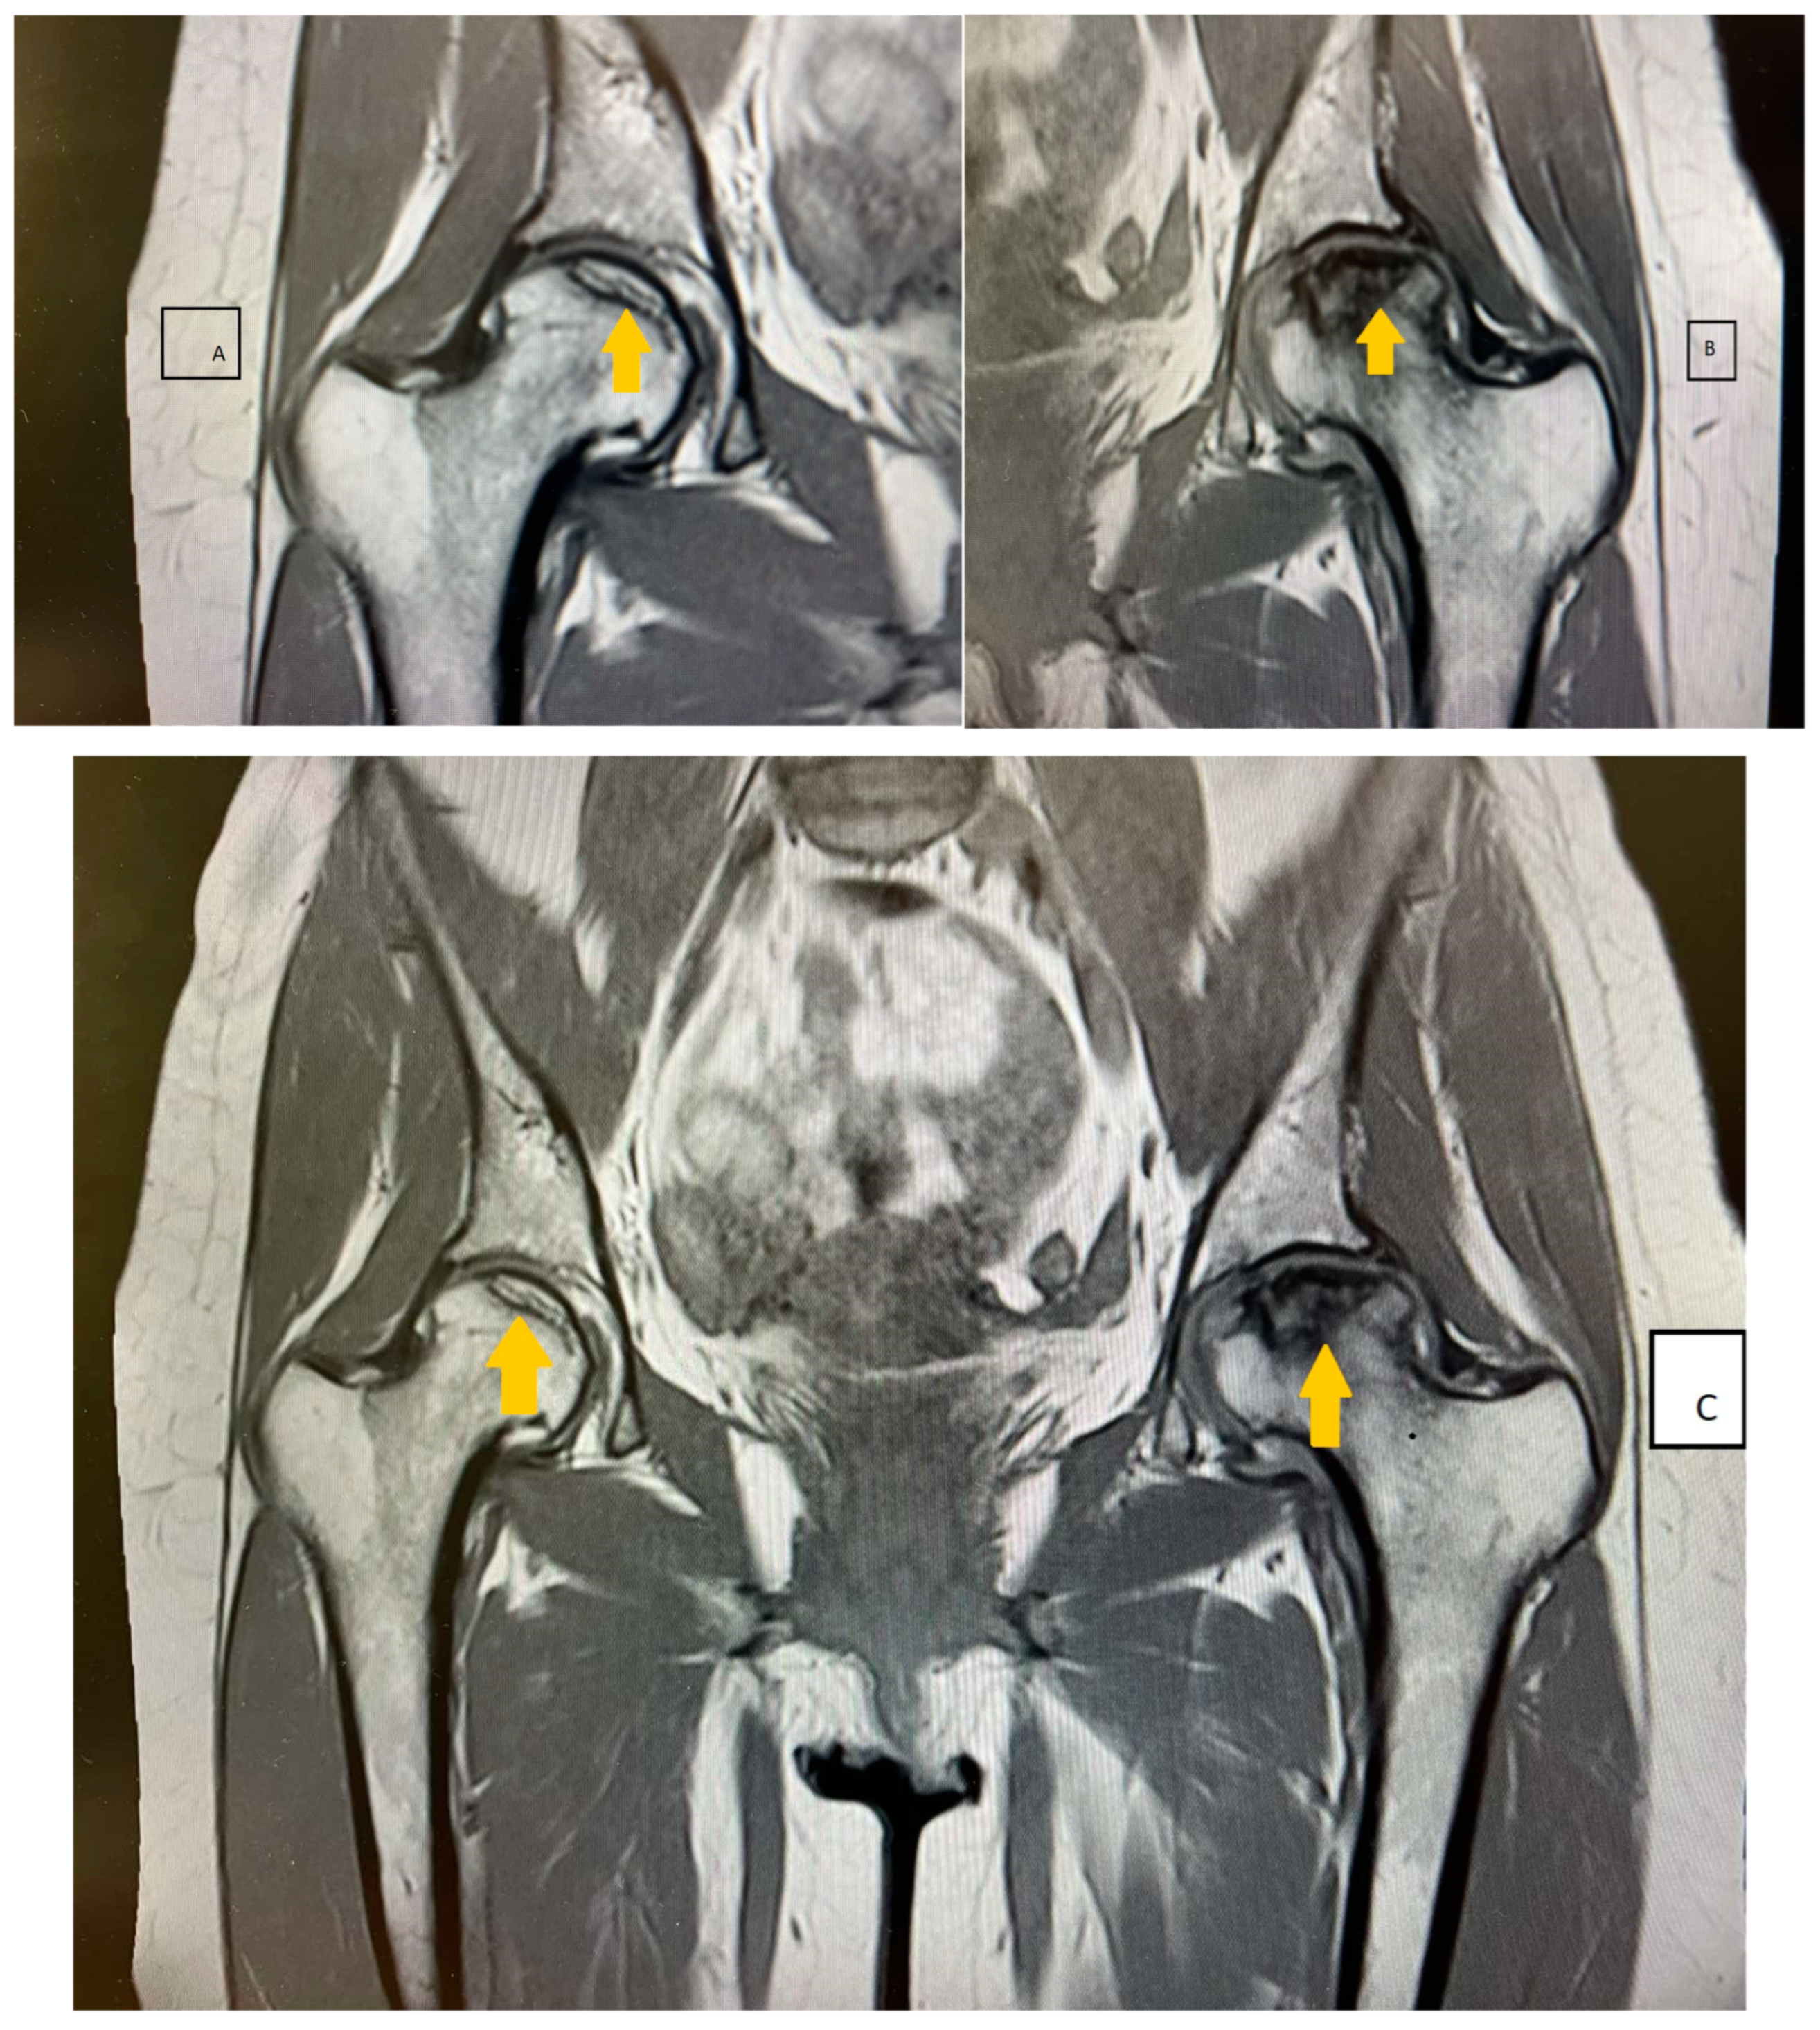

2. Case Presentation